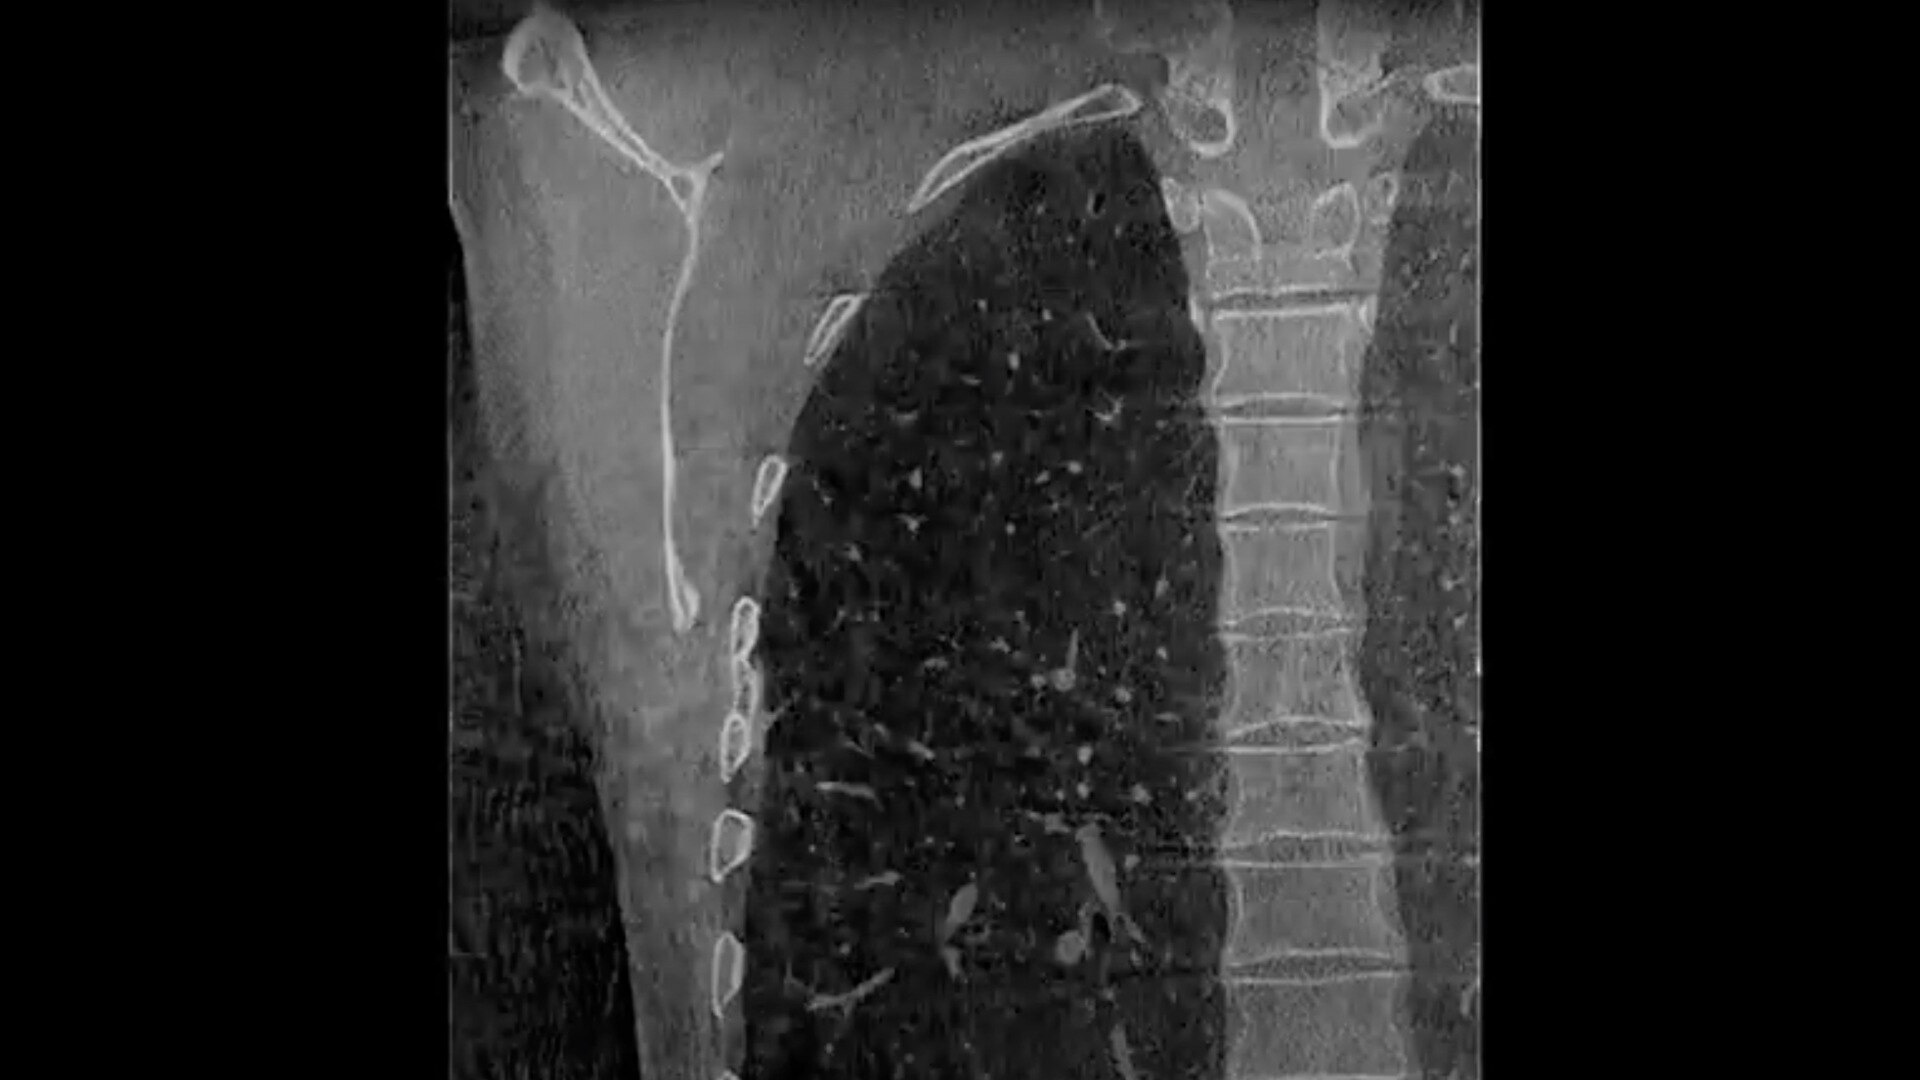

Más allá de la energía dual

TC espectral con imágenes de GSI para una orientación optimizada y precisa durante las intervenciones

Amplíe las capacidades clínicas con la adquisición de imágenes espectrales de Gemstone con cambio ultrarrápido a energía dual y fotodetección con resplandor residual mínimo.

El procesamiento basado en datos sin procesar alcanza la precisión de la separación de materiales para la caracterización y el acceso a imágenes monocromáticas con mejor visibilidad del contraste y con una reducción de los artefactos metálicos.